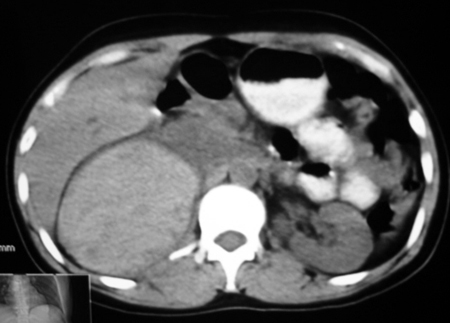

以下是引用卜一在2009-4-23 15:43:00的发言:[br]考虑右肾包膜下血肿,不排除占位病变伴出血可能,建议进一步检查。